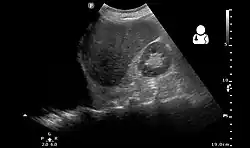

Ultrasonography may be used to detect hemothorax and other pleural effusions. This technique is of particular use in the critical care and trauma settings as it provides rapid, reliable results at the bedside.[23] Ultrasound is more sensitive than chest x-ray in detecting hemothorax.[25] Ultrasound can cause issues in people who are morbidly obese or have subcutaneous emphysema. When CT is unavailable in the current setting or the person cannot be moved to the scan, ultrasound is used.[3]

Ultrasound scan of the chest showing a left-sided hemothorax -